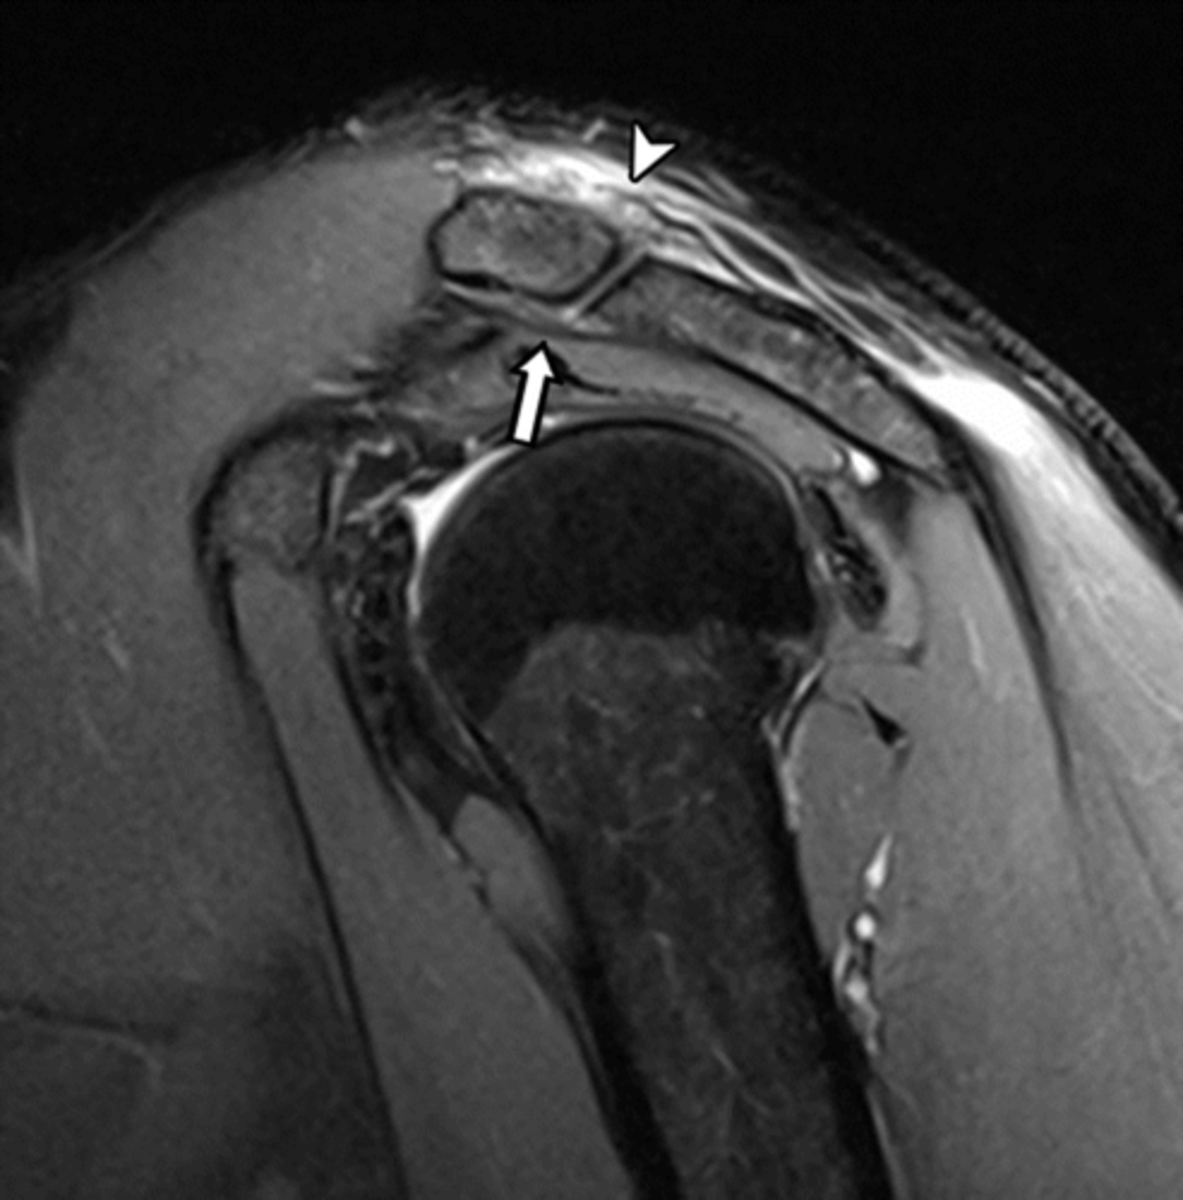

Coronal view of an AC joint separation (grade II sprain) -- an MRI allows us to see the torn ligaments, fluid accumulation, swelling, and get a good sense of the edge of the joint to see how healthy the cartilage is

What is this image depicting? Why is an MRI helpful vs. an x-ray?

Sagittal view of an AC joint separation (grade I-II) -- torn ligaments (sitting on top of the ACJ) buckle and get wavey (when they should be straight and tight normally) and inflammation is also present on the bottom side of the joint

What is this image depicting? How do you know?